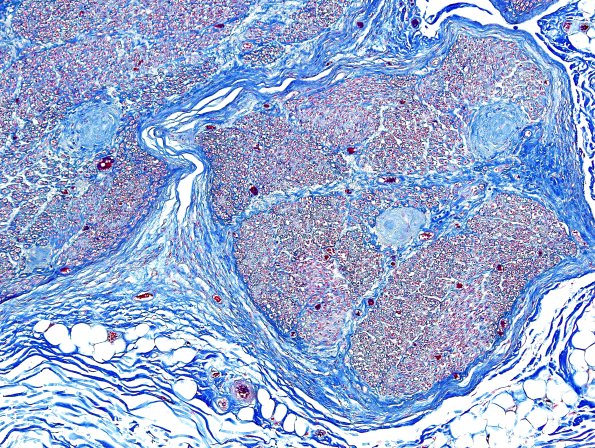

6B2 Renaut body (CIDP, Case 6) L Brachial Plexus Trichrome 5

6B2,3 Higher magnification images (Trichrome)